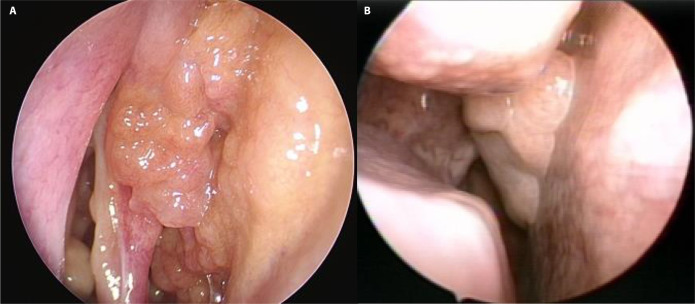

Results: Among 21 patients (17 males, 4 females; mean age 46.5 years), 11 cases (52.4%) exhibited bilateral origins (REAH_bi) in the superior nasal septum and olfactory cleft, while 10 cases (47.6%) presented as isolated unilateral lesions (REAH_uni). REAH_bi was significantly associated with asthma (p = 0.012), prior sinus surgery (p = 0.002), and inflammatory polyposis (p = 0.002) compared to REAH_uni. Elevated preoperative serum eosinophil levels and JESREC scores were also noted in REAH_bi cases (p = 0.021 and <0.001, respectively). Neither group showed recurrence during a mean follow-up of 11.91 months.

Conclusion: Bilaterally originating REAH in the superior nasal septum and olfactory cleft demonstrates pronounced type 2 inflammatory characteristics, suggesting potential differences in pathogenesis compared to unilateral REAH. These findings underscore the need for further investigation into REAH pathophysiology and emphasize the importance of bilaterality in clinical assessment.